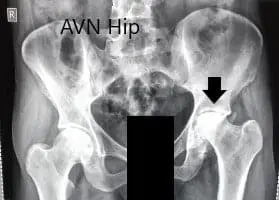

Routine blood investigations were performed and an X-Ray of the pelvis work both hip bones was obtained in the anterior-posterior and lateral views. There was marked left hip joint space destruction. The contour of the left head of the femur was nonspherical. There was marked sclerosis and subchondral cysts. Avascular necrosis of the hip joint was suspected.

Preoperative X-ray of the pelvis with both hips in anteroposterior view